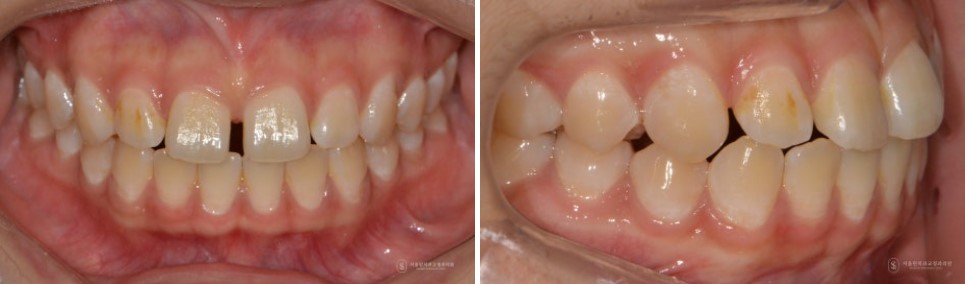

정중이개의 실제 치료 사례

이제 실제 치료 사례를 통해 정중이개가 어떻게 개선될 수 있는지 살펴보겠습니다.

이번 케이스는 정중이개의 원인이 복합적으로 존재하던 경우입니다.

이러한 문제를 해결하기 위해 먼저 아래 사랑니를 발치하고, 교정용 미니스크류를 이용해 아래 치열 전체를 뒤로 보내는 작업을 진행했습니다.

그 다음 단계로, 위 앞니가 아래 앞니를 안정적으로 잘 수용할 수 있도록 아래 앞니의 치아 크기를 치간삭제를 통해 적절히 줄여 비율을 맞추었습니다.

이후 교정적으로 위 앞니 사이의 공간을 닫아 정중이개를 해소하고, 마지막으로 재발 방지를 위한 상순소대 절제술을 시행했습니다.

그 결과, 단순히 앞니 사이 공간만 닫힌 것이 아니라 정중이개, 교합, 위아래 앞니 크기 밸런스까지 함께 개선되는 치료 결과를 얻을 수 있었습니다.